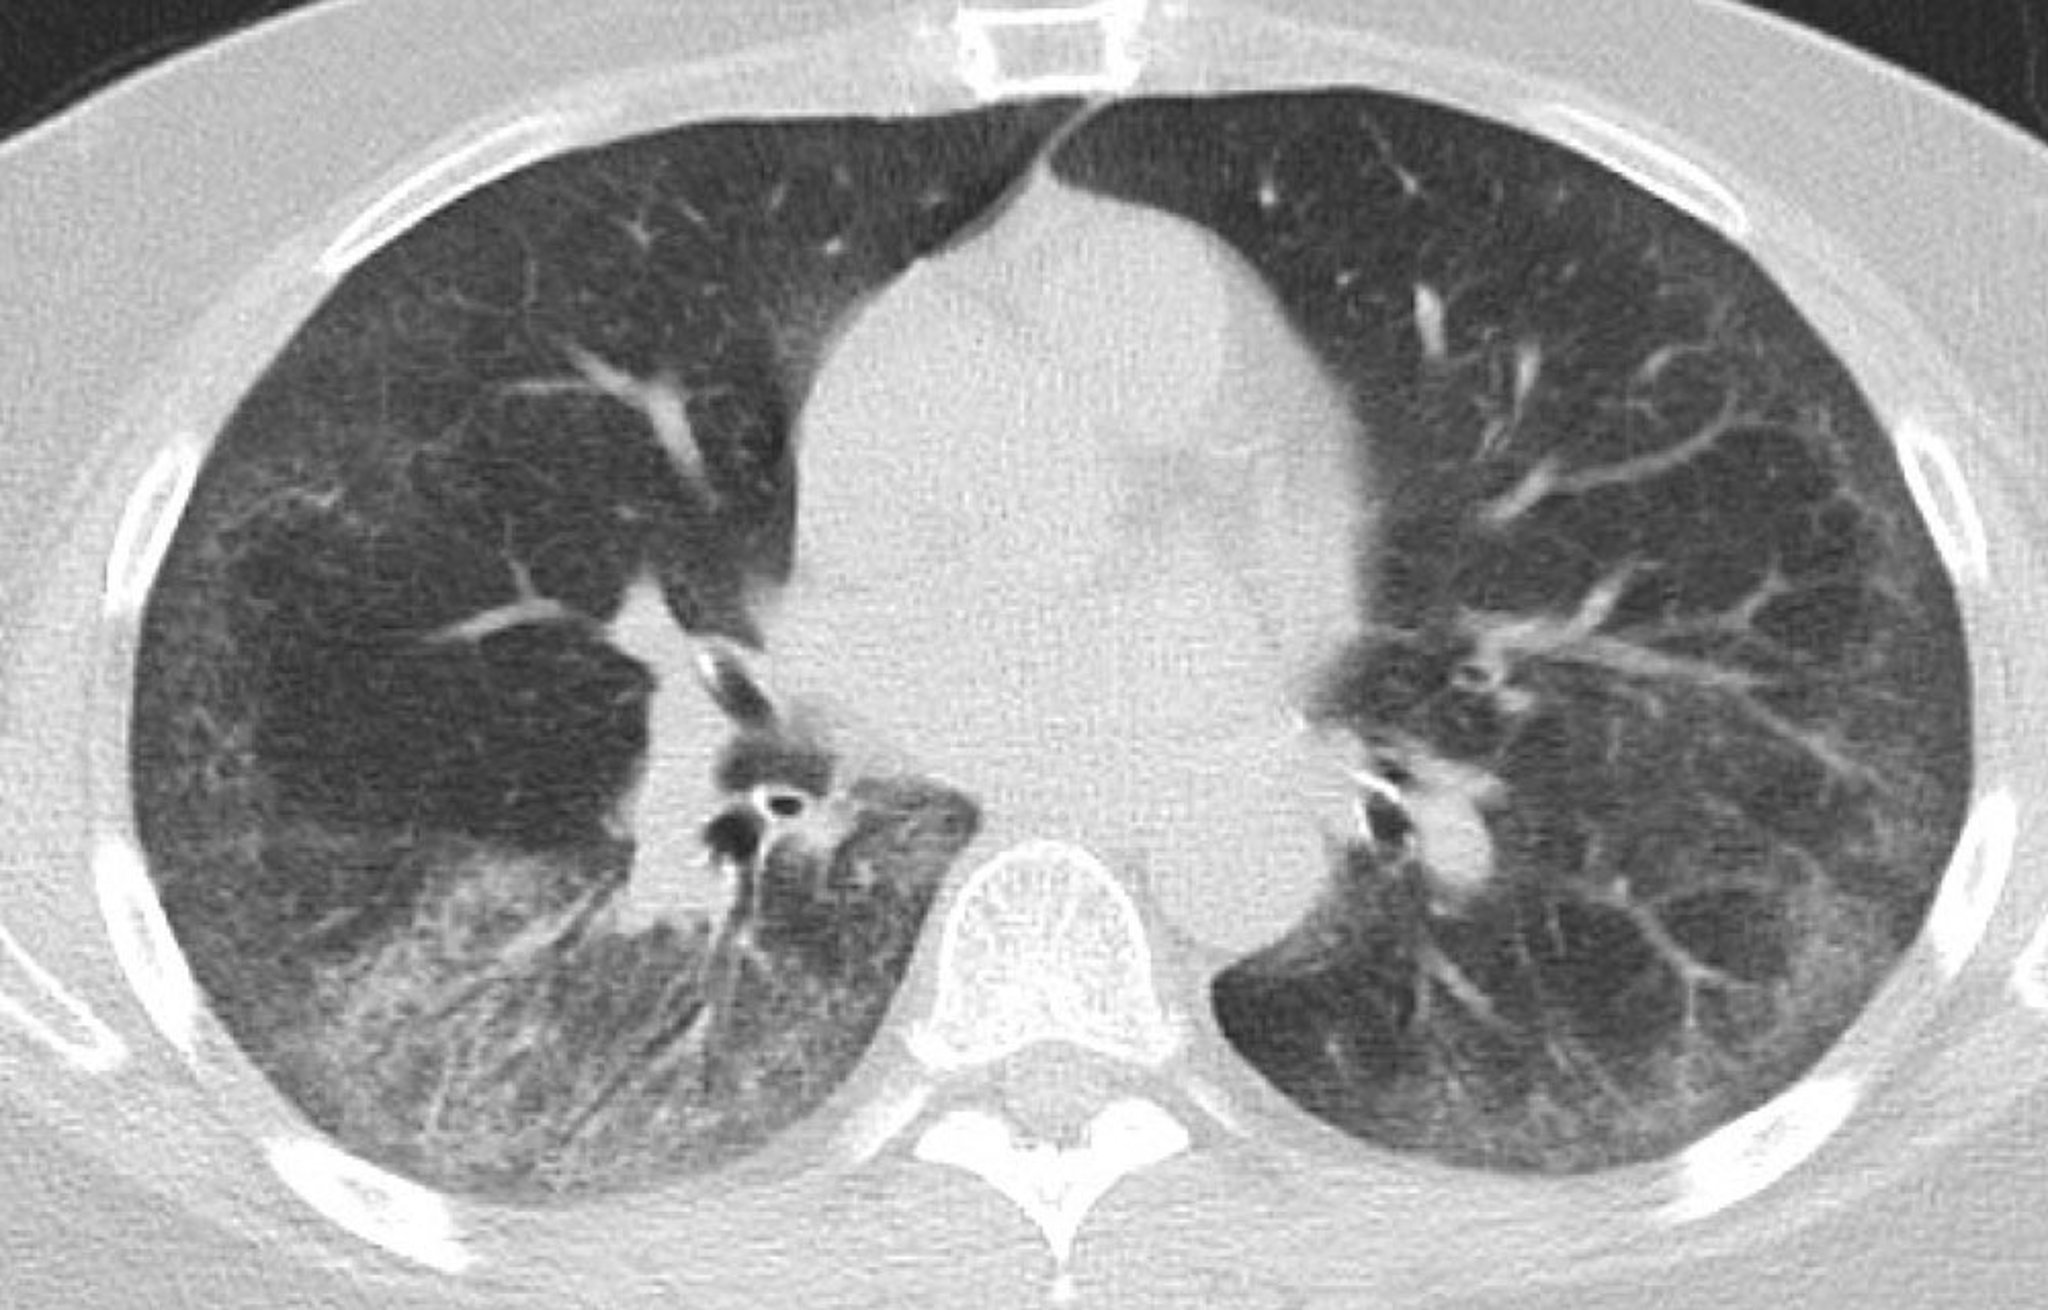

Maladie pulmonaire interstitielle (TDM thoracique)

Cette TDM montre des opacités symétriques bilatérales en verre dépoli du lobe inférieur avec des zones de réticulation sous-pleurale fine; une bronchectasie légère de traction dans les deux poumons avec épargne sous-pleurale; et quelques ganglions lymphatiques thoraciques épars.

Photo courtesy of Kinanah Yaseen, MD.